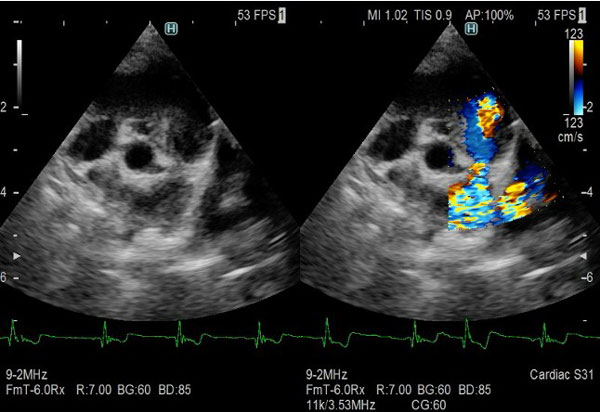

• 循環器疾患(インターベンションによる治療を含む)

肺動脈狭窄症